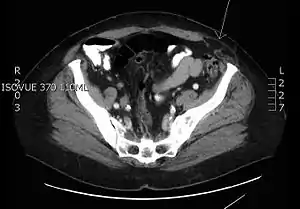

| Transverse CT image of the abdomen in a patient with a Spigelian hernia (arrow). | |

Ultrasound Imaging or a CT Scan will provide better imaging for the detection of a hernia than an xray.[6] The diagnosis of a Spigelian hernia is traditionally difficult if only given a history and physical examination.[7] People who are good candidates for elective Spigelian hernia surgery, not only but also, after receiving an initial diagnostic consultation by a licensed medical professional, will be advised to see a physician to schedule surgery.